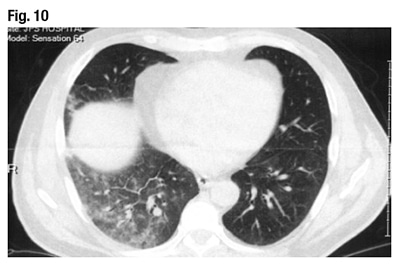

Dr. Larsen displayed the CT scan of the patient’s lungs (Fig. 10). “Even I can recognize there’s something wrong in the right lung,” he said. “This is just diaphragm, of course, but there is some sort of patchy, ground glass infiltrate in the right lung and, looking a little more closely, there probably is even some of the same process going on in the left lung, just a lot more subtle.” The problem appears to be bilateral.